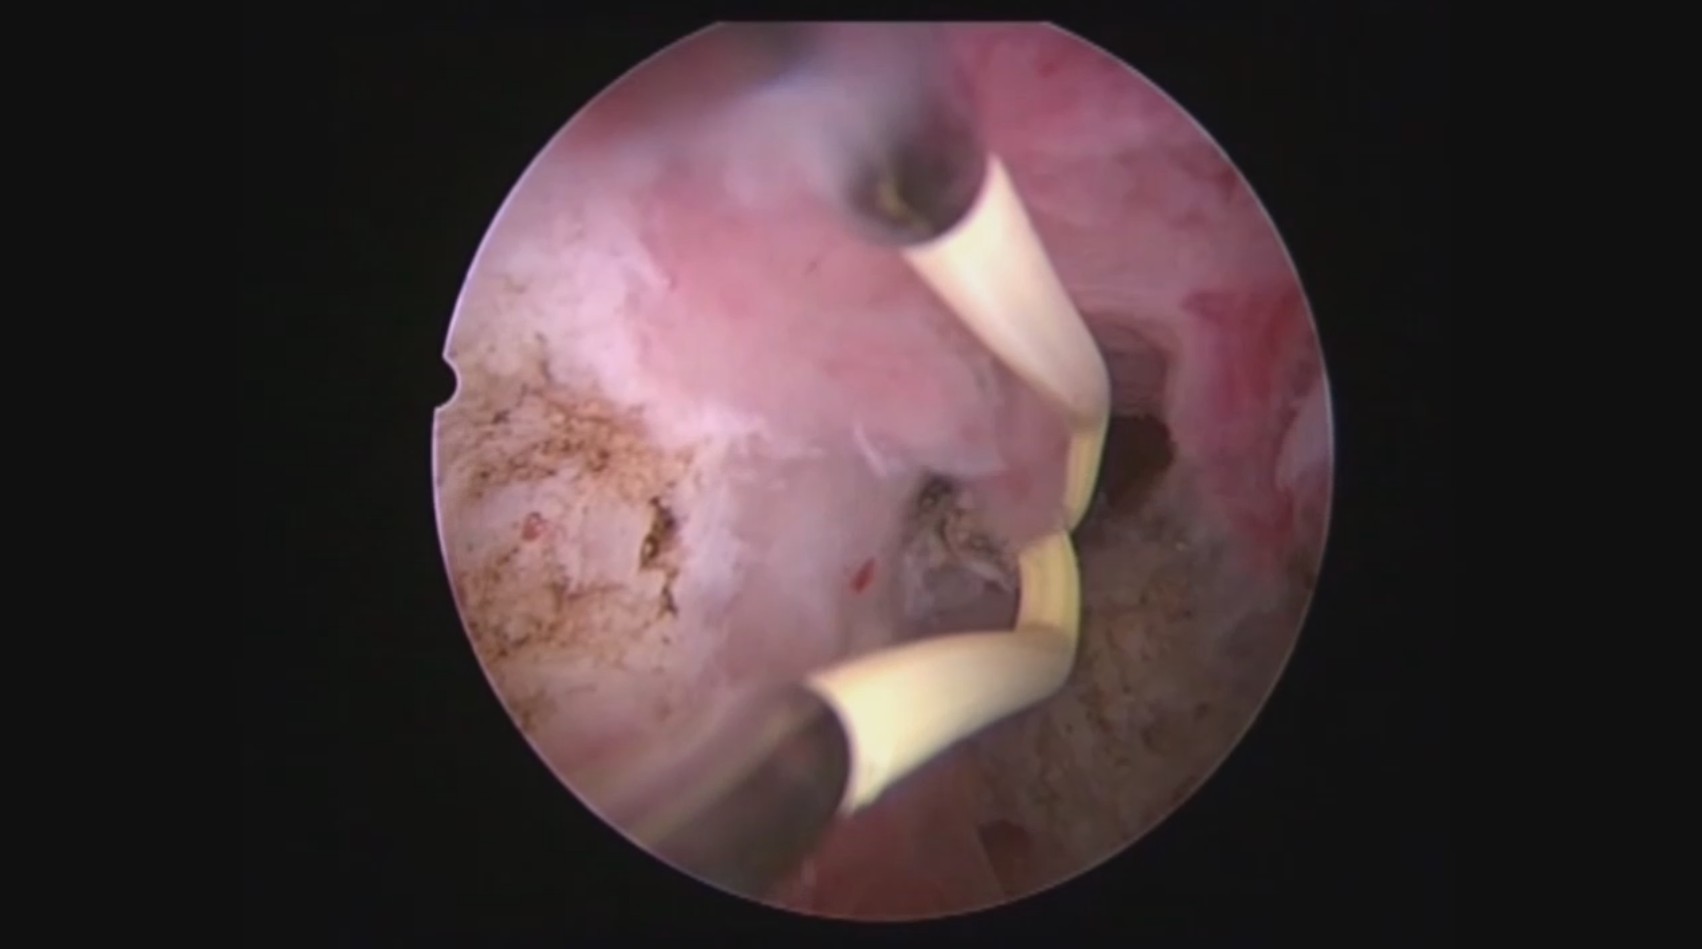

患者32岁,G6P0,继发不孕,2017年8月行宫腔镜探查,发现宫腔两侧及宫底致密粘连,尤其是宫腔右侧多重粘连,宫腔狭小。单极电切分粘,恢复宫腔形态,显露双侧输卵管开口。2018年8月自然妊娠40多天,我在兰州大学附一院生殖中心进修,病人微信发B超给我,大孕囊,胎心微弱,外院疑诊胚胎停育,拟行清宫,嘱病人不要轻易清宫,继续保胎1周,复查B超,胚胎发育正常。病人的信心和坚持成就了她自己和孩子的奇迹,孕期顺利,足月分娩。后病人再次妊娠1次,人流终止妊娠,现41岁,G8P1。